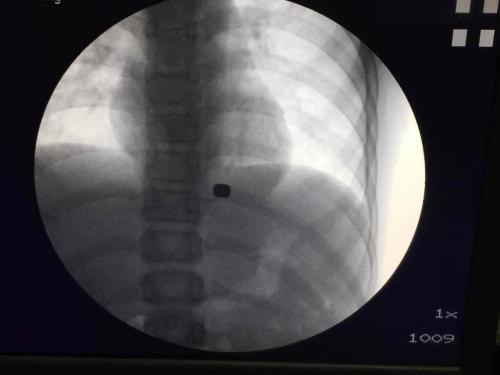

此后,强强便出现了上腹疼痛的症状,其父母带其去医院检查发现,磁铁掉在强强食道下段和胃底。原以为可以通过大便排出,但两天后,10月30日,强强再次去医院做X光检查发现,两块磁铁还在原位,也没有要掉下去的迹象。同时,胃镜检查还发现磁铁所在部位已经有溃疡出现。当地医生告诉强强父母,内镜无法将两块磁铁取出,只能用外科手术才能解决。而外科手术就意味着要开胸,是个大手术,强强的父母不愿儿子接受这样的手术,拒绝了当地医院的建议。辗转多地求医后,11月6日来到华西医院。

据川大华西医院消化内镜中心主任胡兵教授介绍,强强来到华西医院时,离强强吞下磁铁已近10天。通过检查,他发现,跌落在强强食管下段贲门处的磁铁与掉落在胃底的磁铁隔着胃底肌层紧扣在一起,同时还造成了一个0.1厘米的穿孔。并且,因为长时间停留,贲门和胃底部的组织已经将两块磁铁“包裹”起来,磁铁深深嵌在肉里,根本看不到磁铁的边缘,而且两块磁铁相互吸引的磁力很大,周边组织也贴得很紧,消化内镜的夹子根本夹不住,即便是开胸手术,也可能找不到两块磁铁?!叭绻布械幕?,会夹到磁铁周围的组织,这样孩子也很危险,而且,硬夹出来的话,必须挖开磁铁周围的组织,这样会造成一个更大的洞,手术后能不能把这样一个大洞封好,娃娃会不会大出血,都是未知因素?!?/p>

外科手术不能做,内镜钳子夹不住,怎样才可以在损伤最小的情况下,把强强身体里的两块磁铁取出来呢?胡兵教授绞尽脑汁,不经意间一抬头,他眼睛一亮,办公桌上,放着一块环形物件,那也是一块磁铁,而且是一块磁力很大的磁铁,是他几天前刚从网上买来准备做其他研究用的,“既然娃娃吞进去的是磁铁,那我可不可以用一个磁力更大的磁铁把他们吸出来呢?”昨日上午11点左右,麻醉后的强强被推进手术室,胡兵先用内镜从他食道伸进去,轻轻剥开包裹着两块磁铁的组织,然后,再把自己网上购买的强磁铁严格消毒后,套上一根细线,用内镜缓缓送到强强胃内的两块磁铁旁边。不出所料,中午12点两块磁铁成功取出。(文中强强为化名)

(图片由川大华西医院消化内镜中心提供)